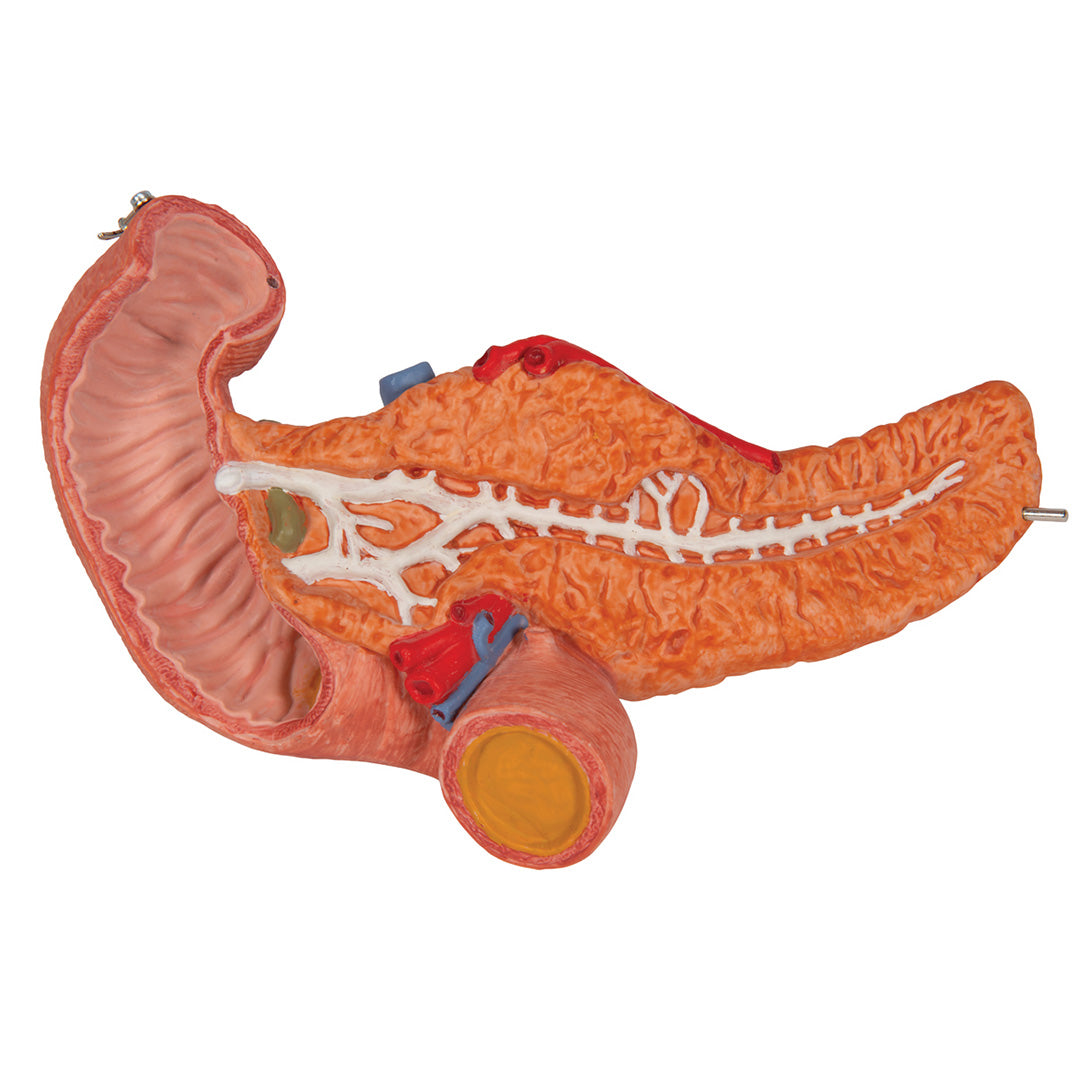

Estómago, en 3 piezas

Estómago, en 3 piezas

El modelo presenta las capas de la pared del estómago desde la cardia hasta el píloro.

La mitad delantera del estómago se puede retirar.

Se presentan:

• Parte inferior del esófago

• Conductos

• Nervios

• Duodeno

• Páncreas

Con soporte.

Peso 0.87 kg.

Dimension 25 x 22 x 12 cm